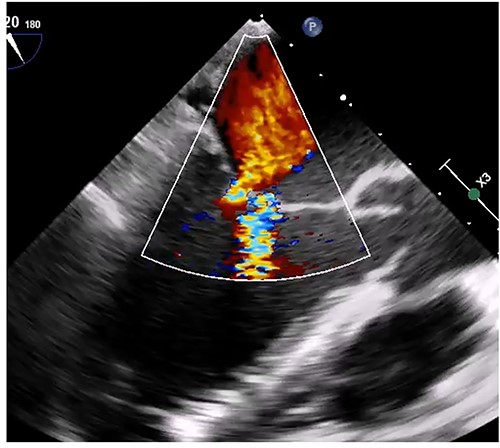

Median sternotomy was performed, and cardiopulmonary bypass was established via aortic and bicaval cannulation. Under cardiac arrest with antegrade cardioplegia perfusion, the LA was examined via the transseptal approach. The LA cavity was filled with the mass that the stalk was attached to the septal wall at the LA side, and the mass was too big and resected in pieces (Fig. 2). The mitral valve leaflet was intact, and the atrial septum was closed. Dilatated tricuspid annulus was fixed using a flexible band (Tailor Flexible band 29 mm, Abbott). After unclamping of the ascending aorta, a transesophageal echocardiogram points out moderate mitral regurgitation due to mitral annulus dilatation (Fig. 3). Cardiac arrest was performed again, and mitral annuloplasty was performed with a semi-rigid ring (Carpentier-Edwards Physio Ring II 26 mm, Edwards) via left atriotomy. His heart sinus rhythm returned to normal with successful weaning from cardiopulmonary bypass. After the transesophageal echocardiogram procedure, no evidence of the mass and residual mitral regurgitation was confirmed (Fig. 4).

Intraoperative transesophageal echocardiogram after the myxoma resection. Moderate mitral regurgitation with annulus dilatation was detected.